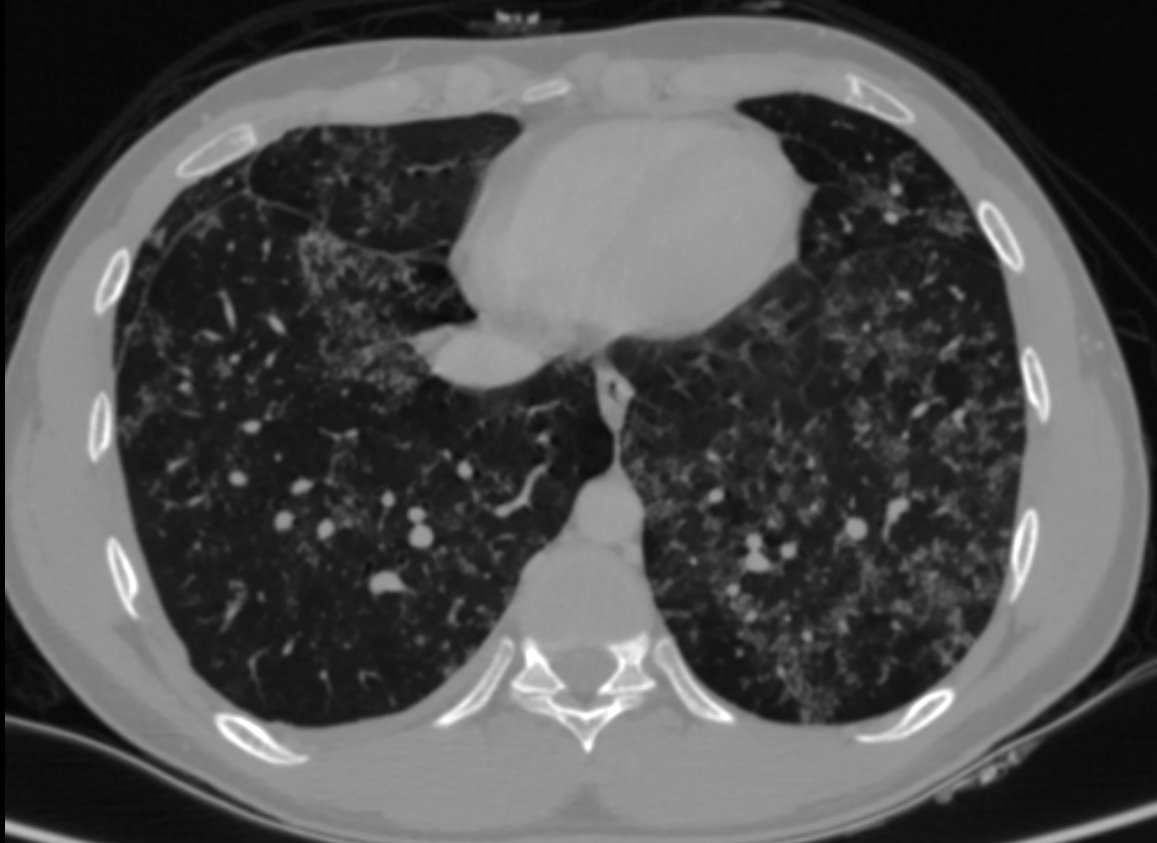

A 23 year old male presented with cough and dyspnoea since 3 months.

• HRCT thorax was performed.

• Numerous patchy nodular parenchymal infiltrates distributed diffusely in all the lung lobes, with a peribronchovascular and subpleural distribution.

• Apical emphysematous changes.

• No significant mediastinal lymphadenopathy seen. No effusion

• Alveolar sarcoidosis

Alveolar sarcoidosis is an atypical pulmonary manifestation of sarcoidosis.

This appearance is thought to result from the aggregation of a vast number of interstitial granulomas rather than representing a true alveolar process.